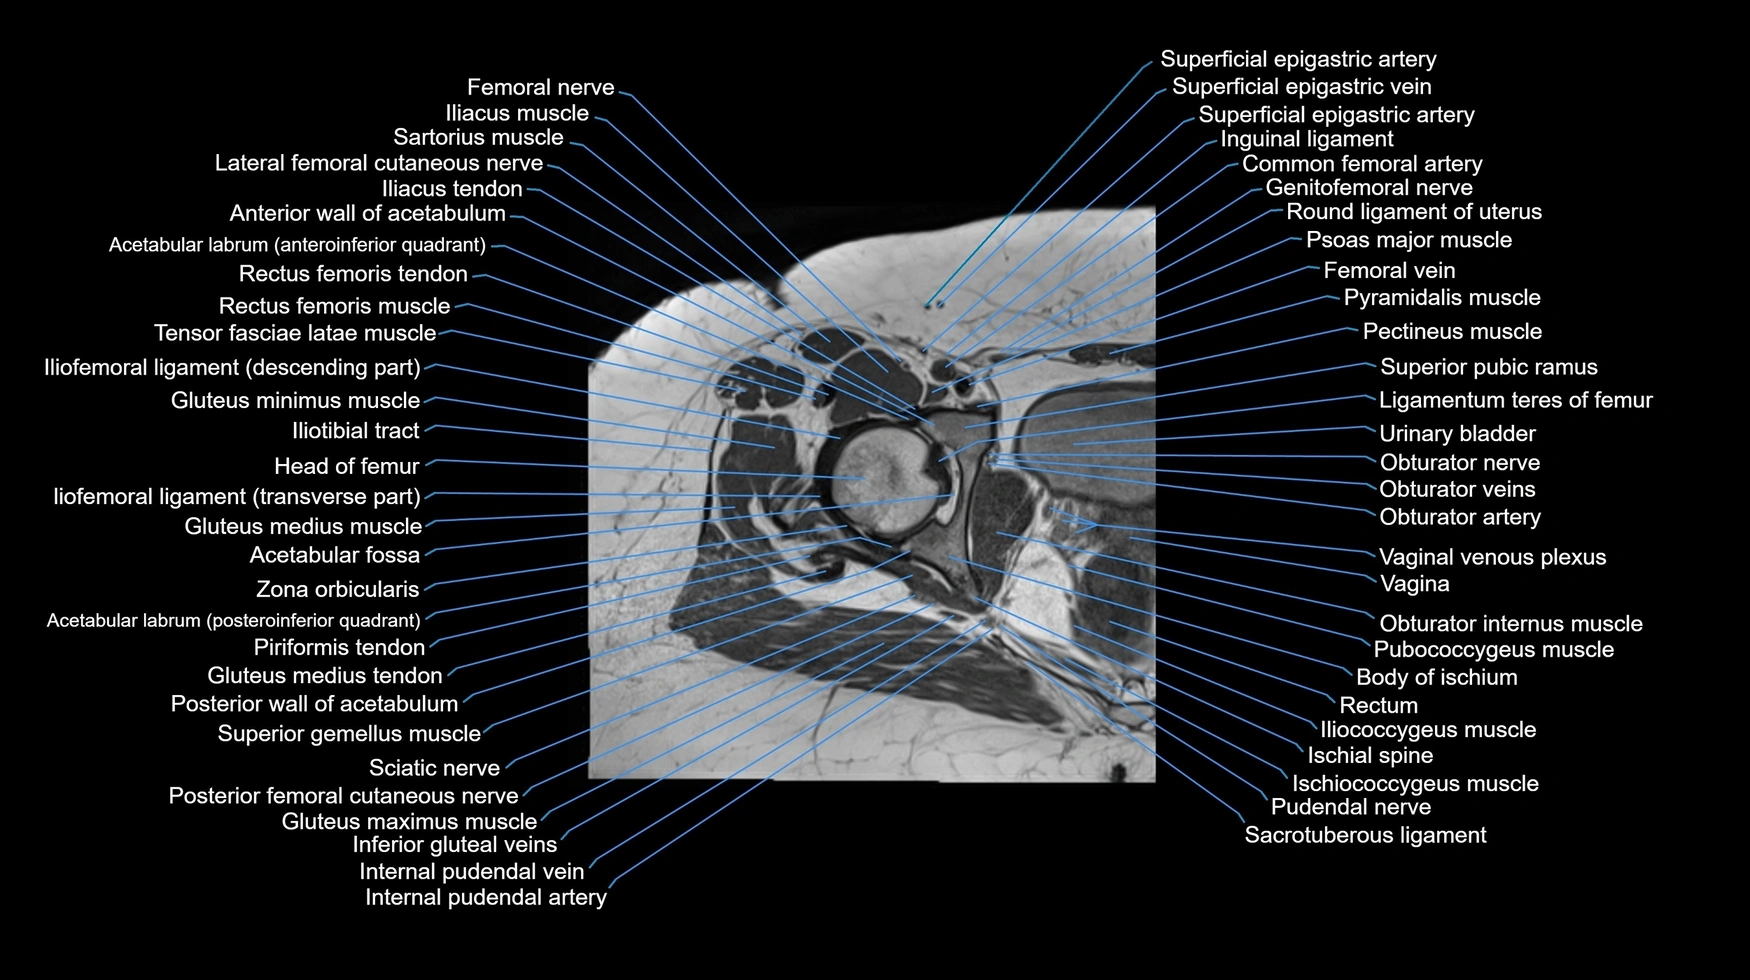

Experience the next generation of cross-sectional anatomy with our advanced 3T MRI, enhanced by AI-powered Deep Resolve reconstruction. Our ultra-high-resolution imaging (0.3–0.7 mm in-plane resolution) combined with ultra-small field-of-view techniques reveals fine anatomical detail with exceptional clarity, redefining anatomical visualization and education.

Explore an advanced library of ultra-high-resolution MRI anatomy, developed from hundreds of repeated scans of volunteers using cutting-edge 3T scanners, dedicated coils, and AI-powered enhancement. These images capture real anatomical detail, revealing even the smallest microstructures while preserving the authenticity of true clinical imaging without over-reliance on virtual labeling.

Learn MRI anatomy like never before—49 body parts, 144 planes

Crystal-clear, high-res images for effective large-screen teaching

All our cross-sectional images are meticulously hand-labeled by professionals with over 20 years of experience in cross-sectional imaging. This is the result of over six years of dedicated work, precision, and passion. Every image is individually checked and verified by senior consultant radiologists from major London NHS trusts, each with relevant subspecialty expertise—ensuring the highest level of accuracy and clinical relevance.